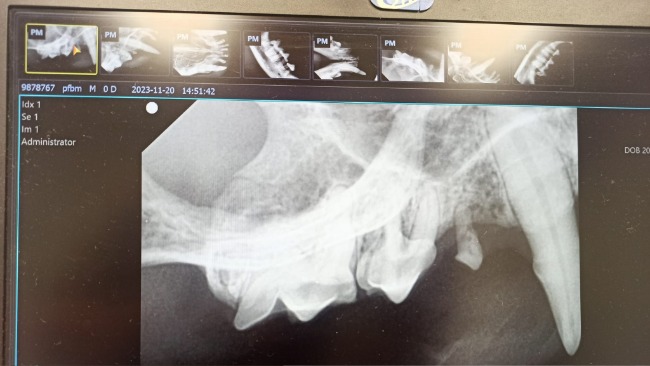

Uszko wymagał pilnej interwencji chirurgicznej, wyłamał się mu kieł, a jak się okazało prawie wszystkie zęby musiały być usunięte.

Zleciliśmy badania krwi - profil rozszerzony oraz potrzebne projekcje RTG.